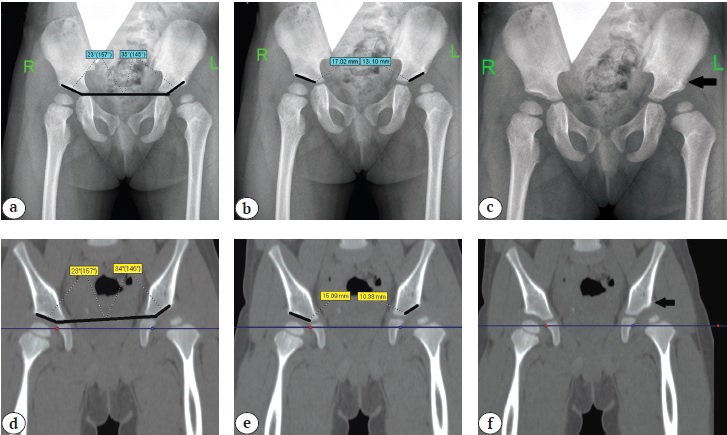

In order to objectify the data, the above-mentioned criteria were calculated using both X-rays and CT slice in the middle of the acetabulum (Figs. 1, 2).

Fig. 2. Determination in patients with Tönnis grade IV DDH based on X-ray and CT results: a, d — acetabular index; b, e — length of acetabulum arch; c, f — absence of bone oriel (indicated by black arrow)